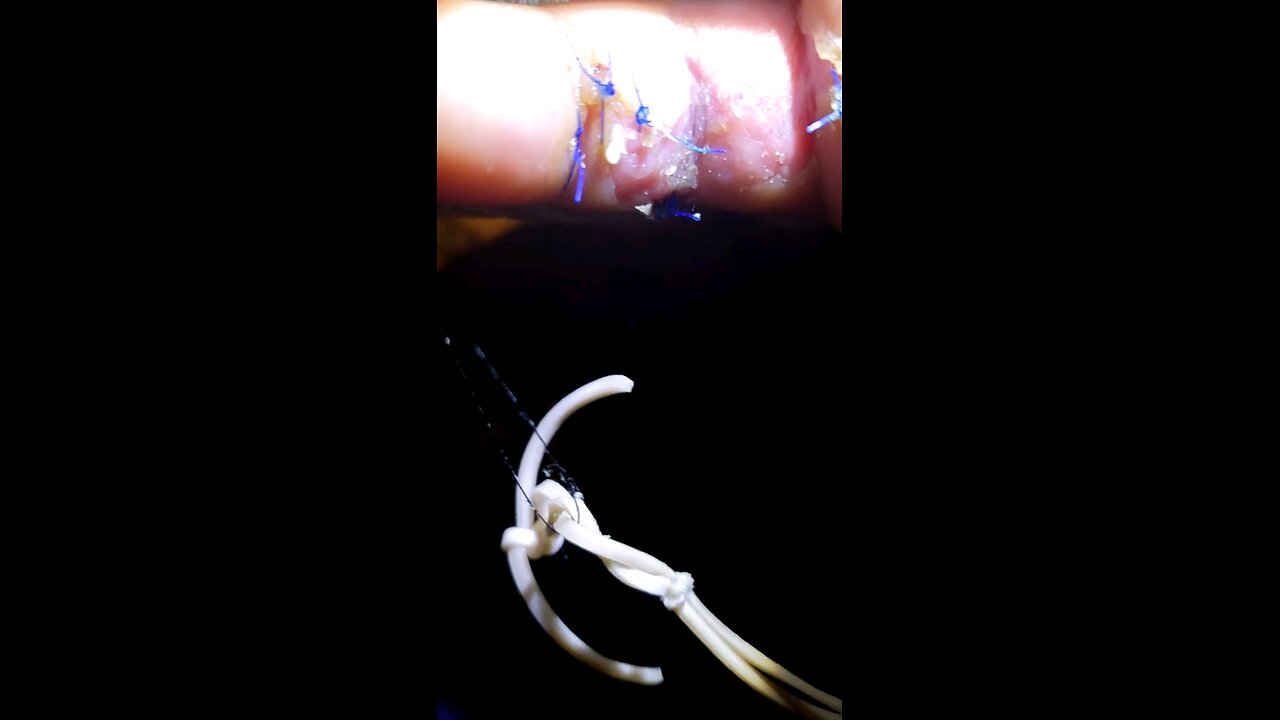

Pocket of pus